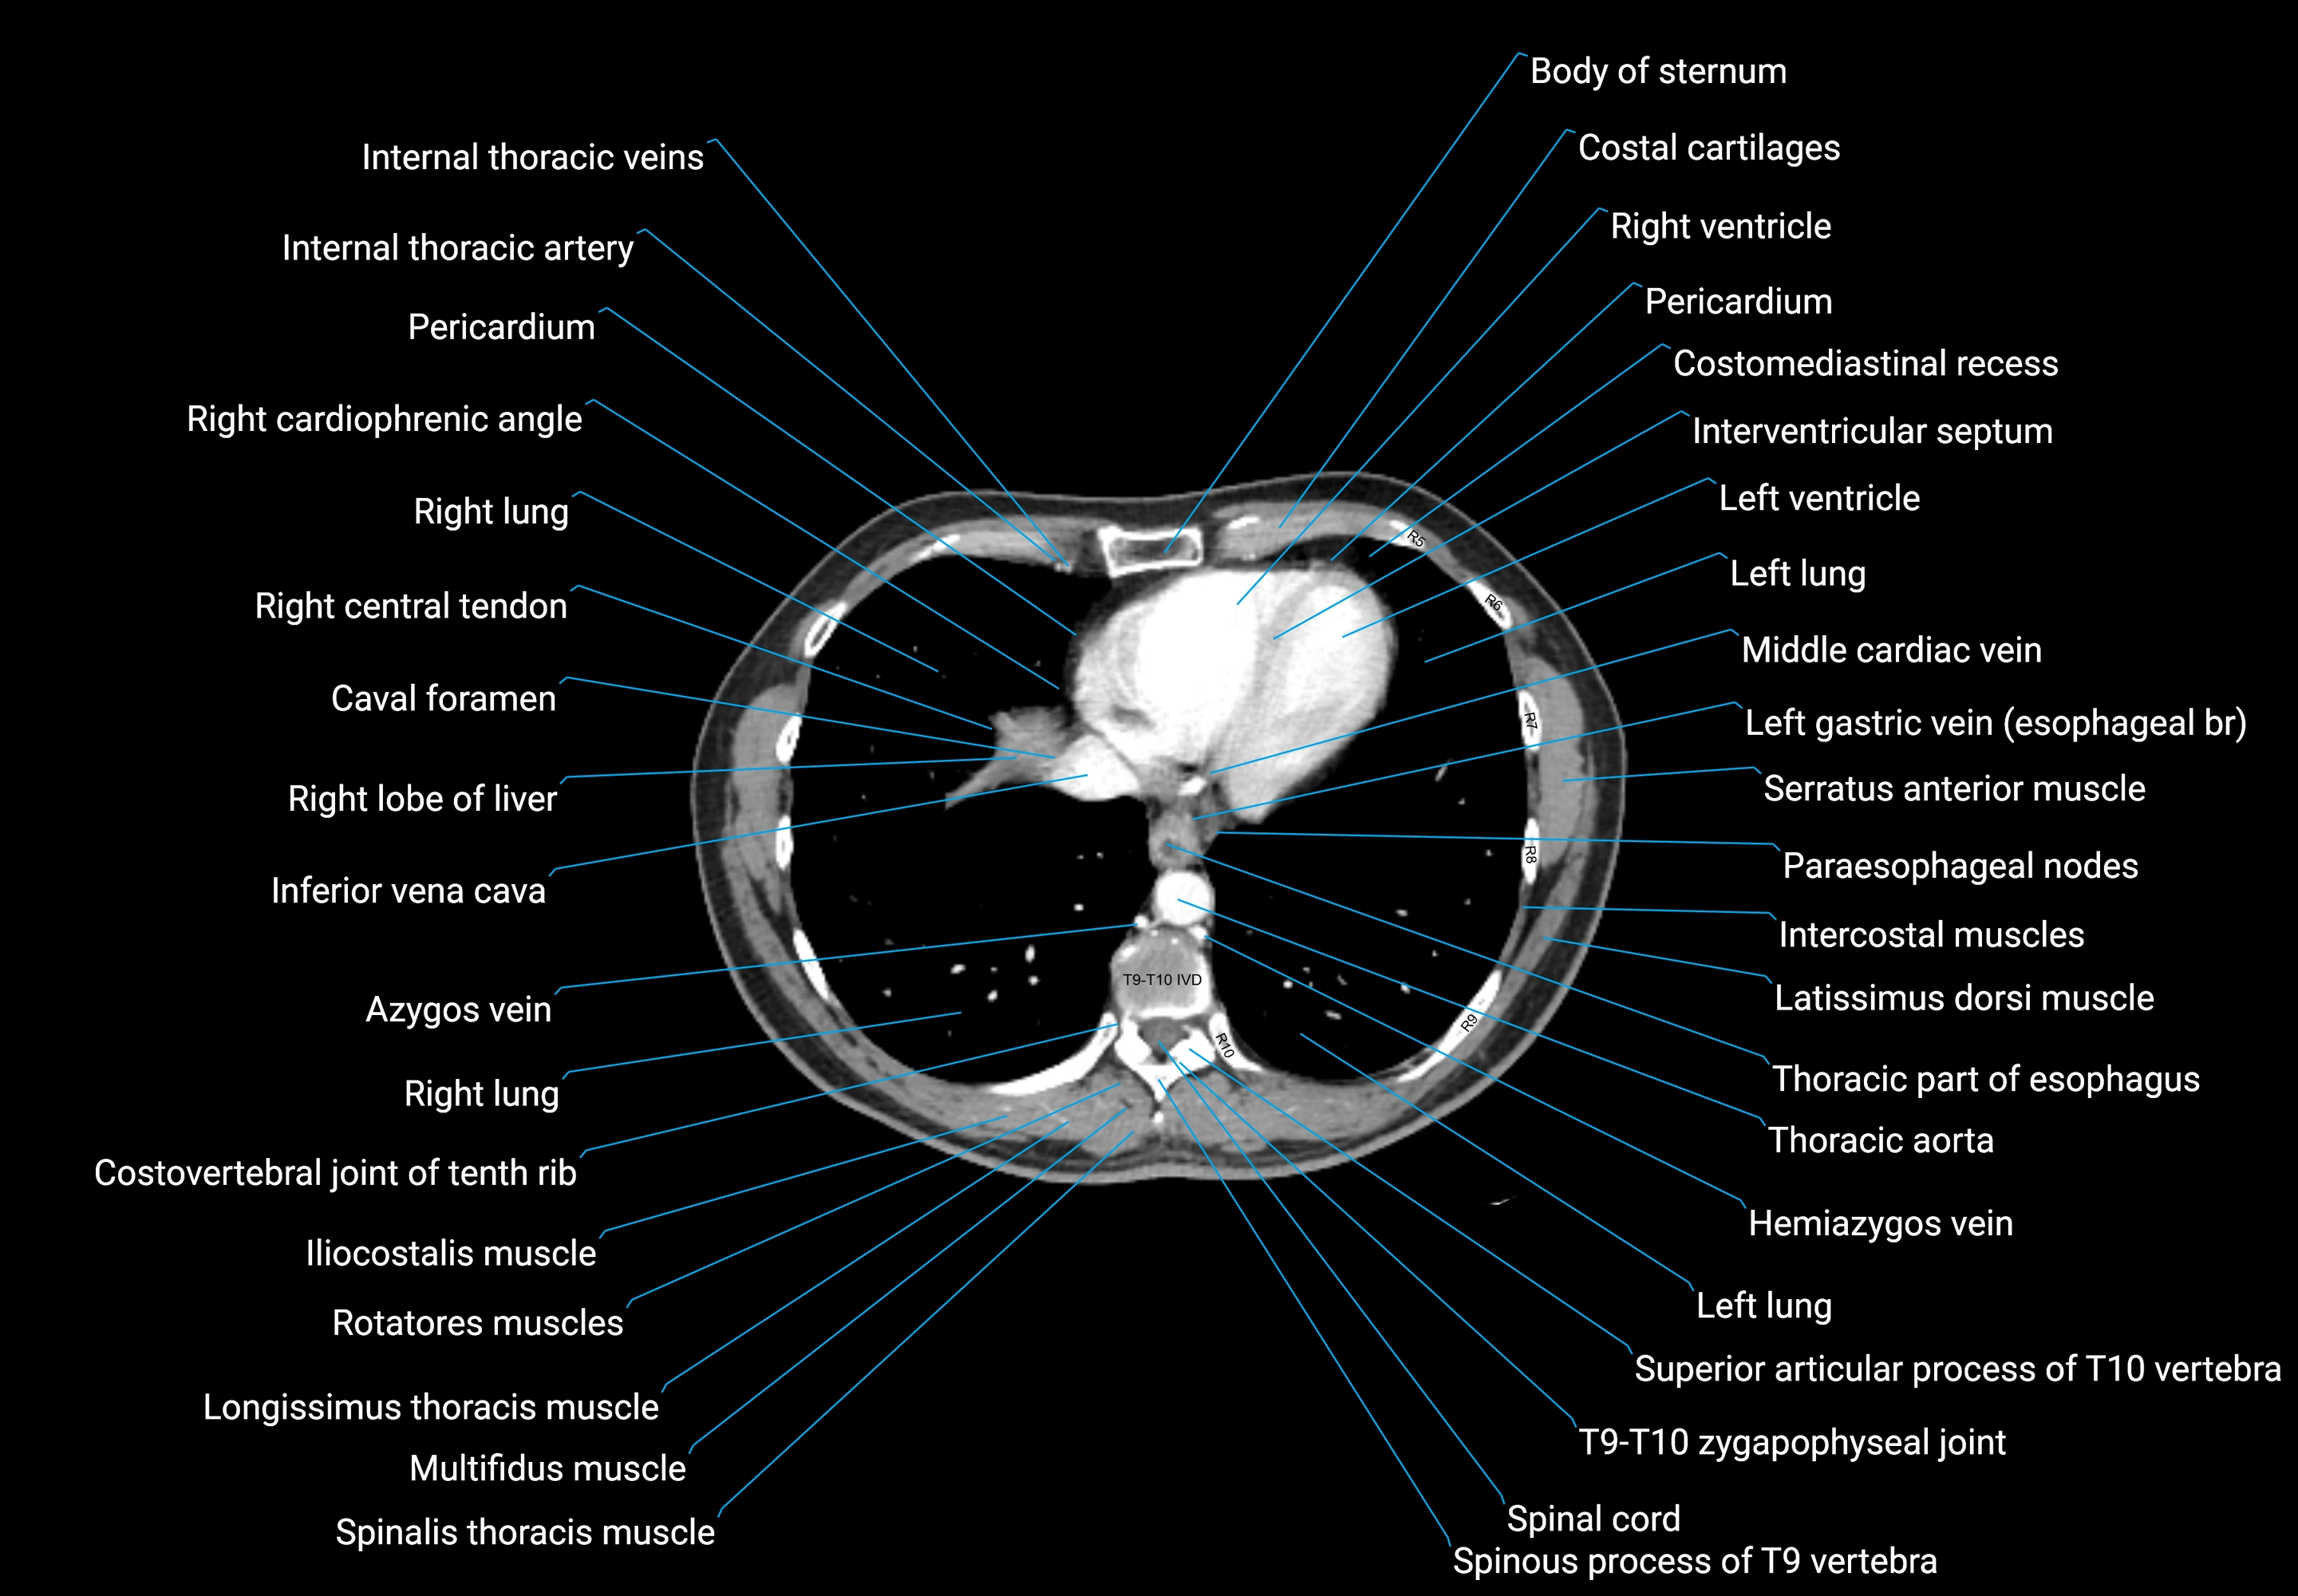

CT images